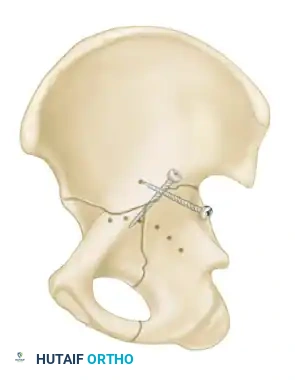

In these cases, two modern strategies are employed:

1. Percutaneous Fixation: Limited column fixation using percutaneous fluoroscopic techniques to prevent gross displacement, allowing the fracture to heal in a stable position prior to a delayed Total Hip Arthroplasty (THA).

2. Acute Total Hip Arthroplasty: Primary THA combined with limited internal fixation (to stabilize the acetabular shell) is increasingly advocated for elderly patients with poor prognostic fracture patterns, allowing immediate full weight-bearing.